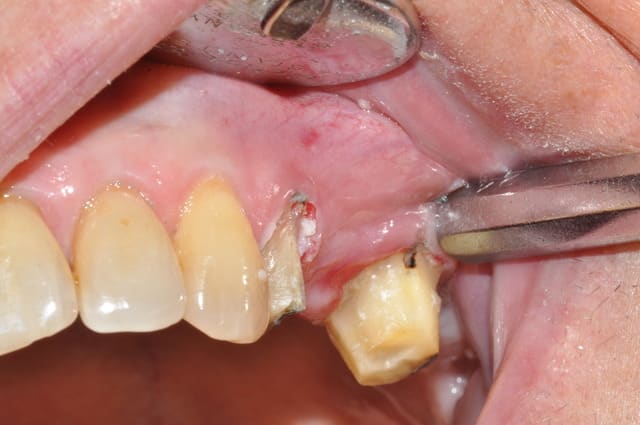

patiente envoyée pour ex° de 26 par un neurologue

souffre depuis 18mois, le bridge à 2ans

Déjà, les couronnes me paraissent bien débordantes

Deuxièmement, je ne vois pas de traitement canalaire sur ces dents. Peut etre souffrent elles de pulpite chronique

patiente revue ce matin

depose du bridge existant sous AL

et empreinte pour provisoire résine en sous occlusion

premiere réaction de la patiente bridge déposé

"çà ma change mes dents de devant, je mords plus pareil"